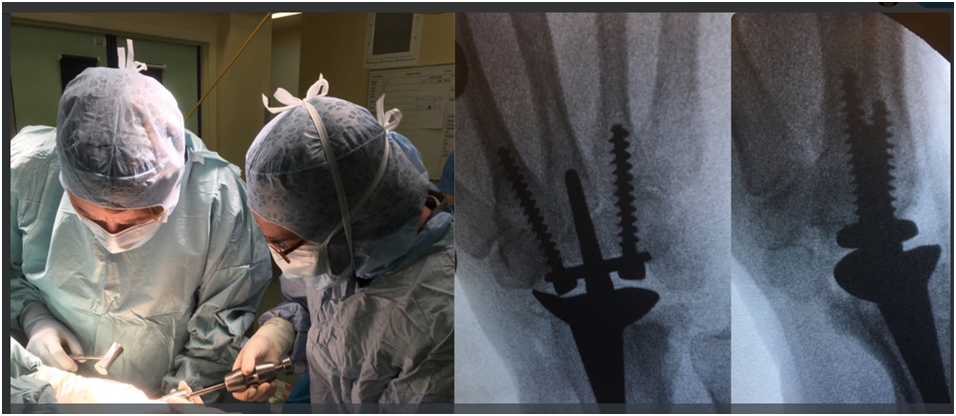

Miss Umarji recently performed the first Total Wrist Replacement at St George’s NHS Trust

After years of pain patient Julie Richardson was delighted to be the forst patient to have a Total Wrist Replacement at St George’s London.